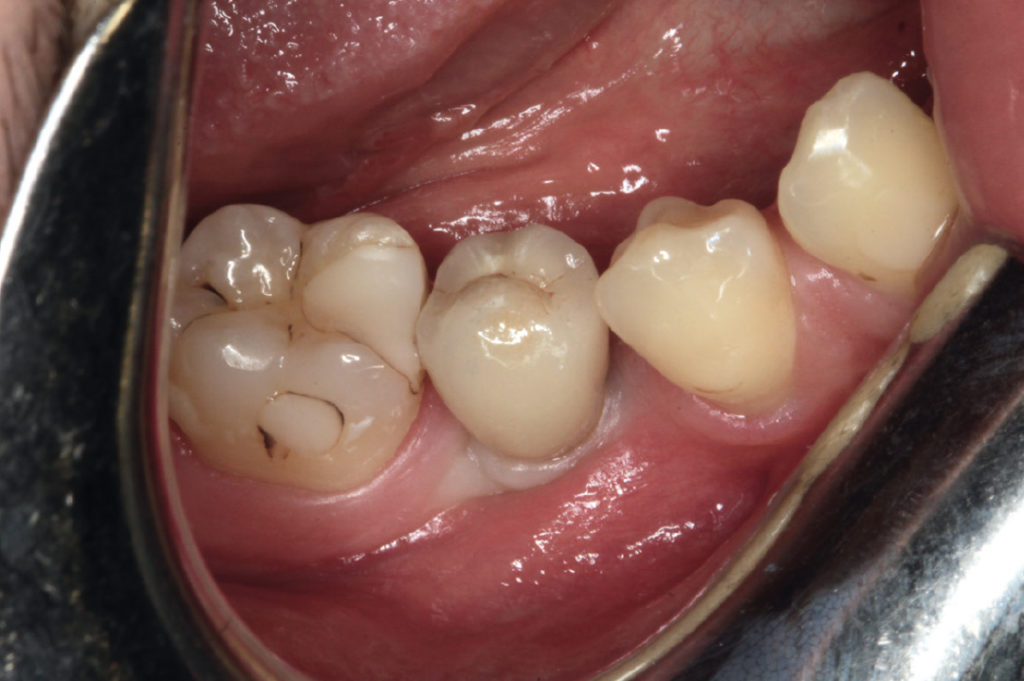

In 2010: deciduous tooth #85

In 2010: deciduous tooth #75